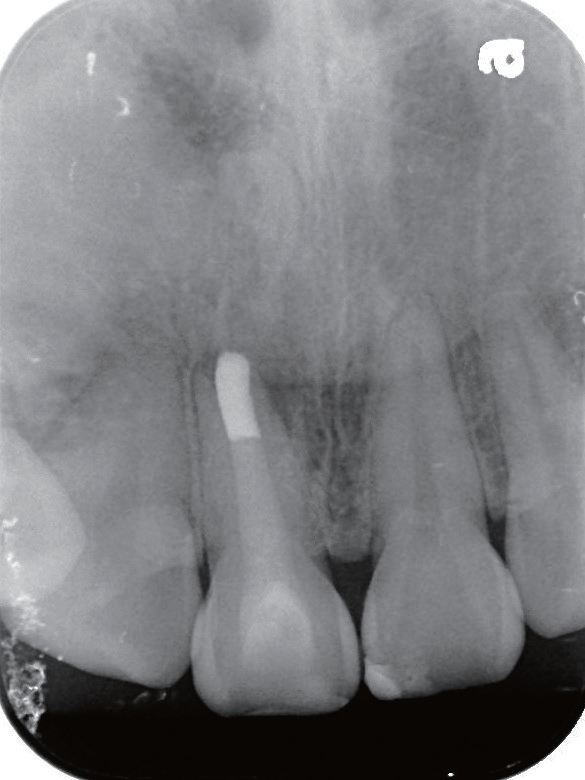

预后   根管治疗后半年(图16)、两年半(图17~18)、三年半(图19)患者前来复诊,可见11根尖恢复良好,已完全愈合,随后进行全冠修复,完成患牙的全部治疗。

图16 根充半年后,患者自觉按压11 根部牙龈时,虽无不适但改善并不明显;X线片显示11 根尖放射性阴影边界变模糊,这是病灶开始愈合的表现

图17 根充两年半后,患者自觉11 牙冠颜色较暗,复诊咨询是否可以进行美白治疗;鉴于治疗前11 唇侧已有数条裂纹,建议用全瓷冠修复较为合适

图18 根充两年半后,患者自觉按压和敲击11时无明显不适,X 线片显示原根尖骨组织缺损逐步愈合,可见根尖牙槽骨板重现

图19 根充三年半后,X 线片可见11 根尖牙槽骨板完整,覆盖突出的牙胶尖,原开口的根尖于治疗后已经闭合